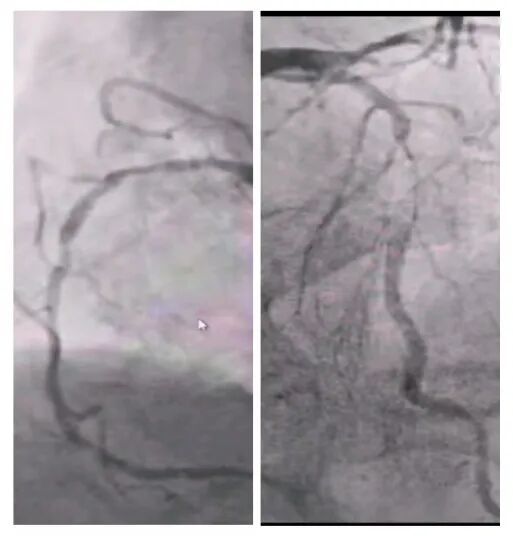

術(shù)后超聲

術(shù)后病理顯示,患者左房腫瘤為良性黏液瘤,完整切除后無(wú)需后續(xù)治療。經(jīng)過(guò)10天的康復(fù)治療,老人順利出院。這一案例中,多學(xué)科團(tuán)隊(duì)通過(guò)術(shù)前風(fēng)險(xiǎn)分層、術(shù)中精密協(xié)作、術(shù)后個(gè)體化護(hù)理,為高齡復(fù)雜心臟疾病患者的救治積累了臨床經(jīng)驗(yàn)